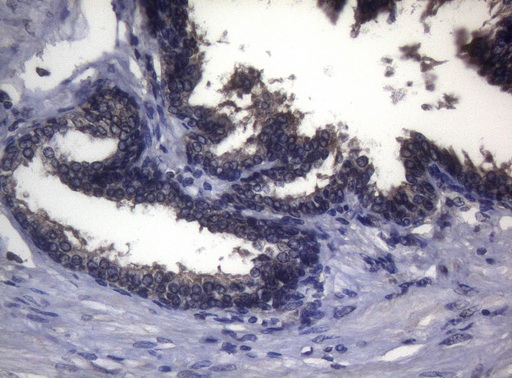

Immunohistochemical staining of paraffin-embedded Human prostate tissue within the normal limits using anti-FOXO3 mouse monoclonal antibody. (Heat-induced epitope retrieval by 1mM EDTA in 10mM Tris buffer (pH8.5) at 120°C for 3min, MA00252) (1:150)